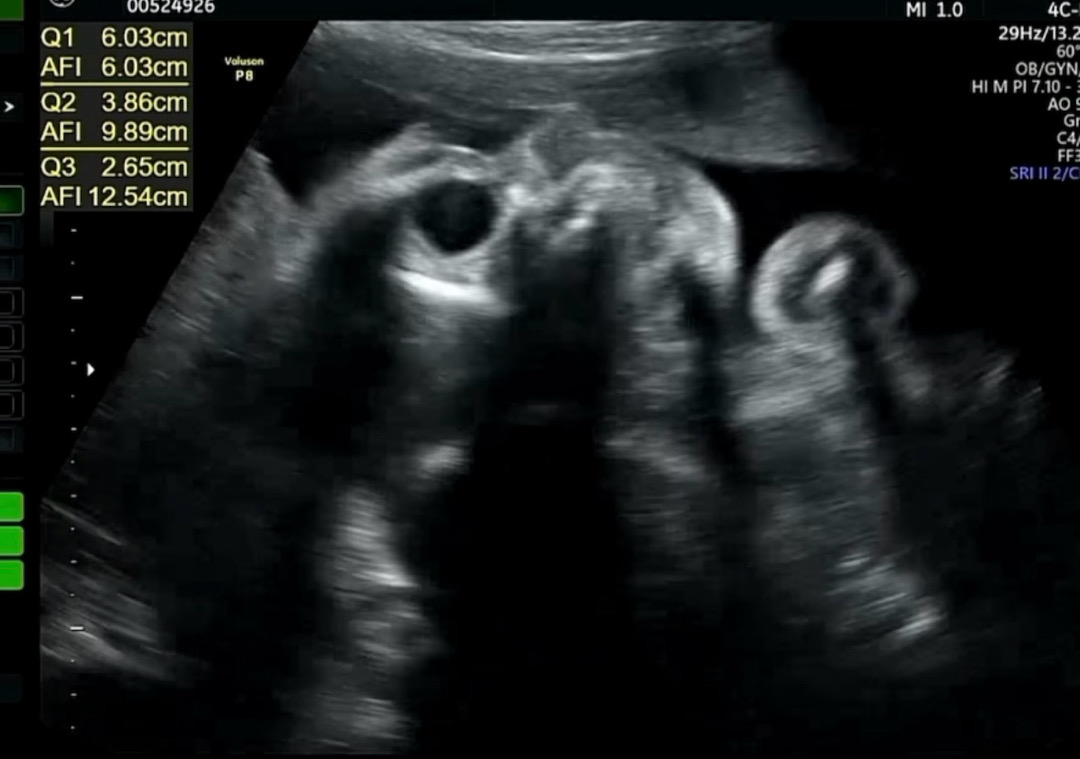

콧대 판독 부탁드립니다

저 사진이 코가 엄마 배를 찌르고 있는게 맞을까요 아닐까요..? 콧대가 높은편일까요..? 콧대가 높네 아니네 움직여서 흔들린거네 아니네 장난으로 내기 하고 있어서 판독 부탁드립니다!!

탈퇴한 유저

코가. 자궁벽을. 찌르고있네욬ㅋㅋㅋㅋㅋㅋㅋ

암것도 모루눈 초산맘인데 제눈엔 높고 모양이 이뻐 보여용 👍🏻